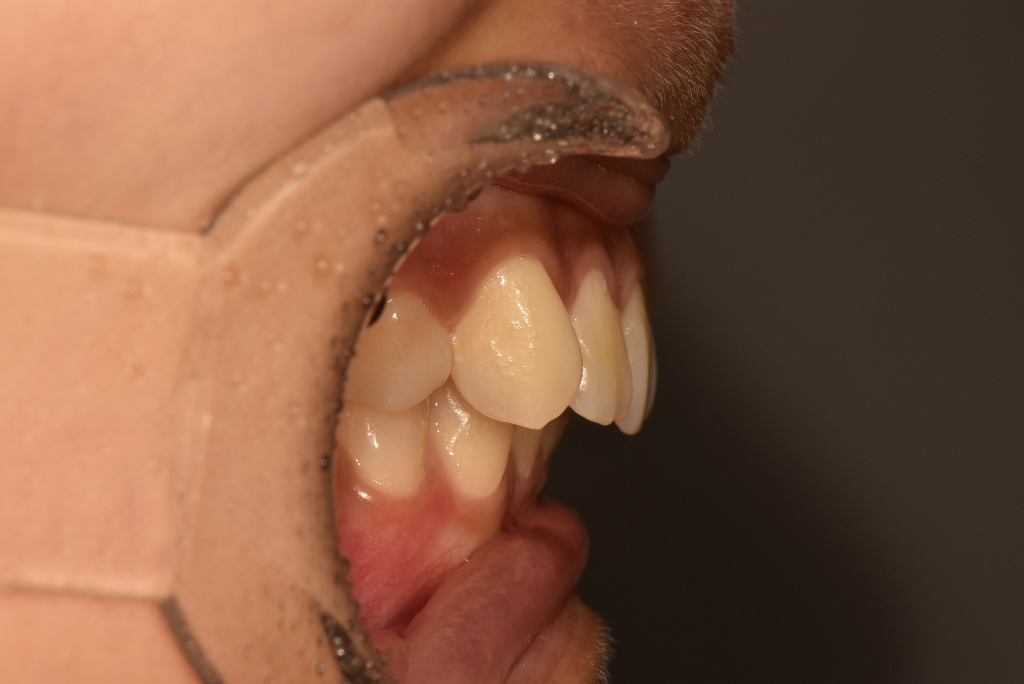

3. 정상교합과 비교해봤을 때 과개교합(deep bite)이 지금 아주 심한 상태는 아닙니다. 다만 위 치아가 아래 치아에 비해 전방 위치하고 있는데 이건 원인이 턱(위턱)때문인지 아니면 단순히 치아가 경사져서 그런지는 방사선 사진을 찍어봐야 판단이 내려집니다.

4. 이렇게 윗니가 좀 튀어나온 경우 전체적인 안모(얼굴외형)에도 영향을 주고 있을 수 있습니다. 입술과 인중 부위가 과긴장 상태로 약간 불룩하게 튀어나와 보일 수 있겠습니다. 말씀주신 것처럼 발치교정이 필요할 수도 있겠습니다.